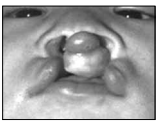

Na literatura, encontram-se várias classificações das fissuras labiopalatinas, de acordo com as estruturas anatômicas envolvidas. No Brasil, a mais difundida e utilizada atualmente é a classificação de Spina que toma por base o forame incisivo.

Assinale a alternativa que apresenta uma fissura pré-forame incompleta unilateral esquerda.

(Octacílio. Novo Tratado de Fonoaudiologia. 3a Edição. E-book)